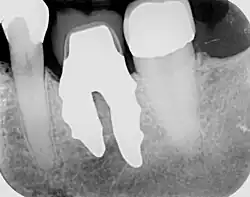

X-ray of root analogue dental implant two rooted left lower molar